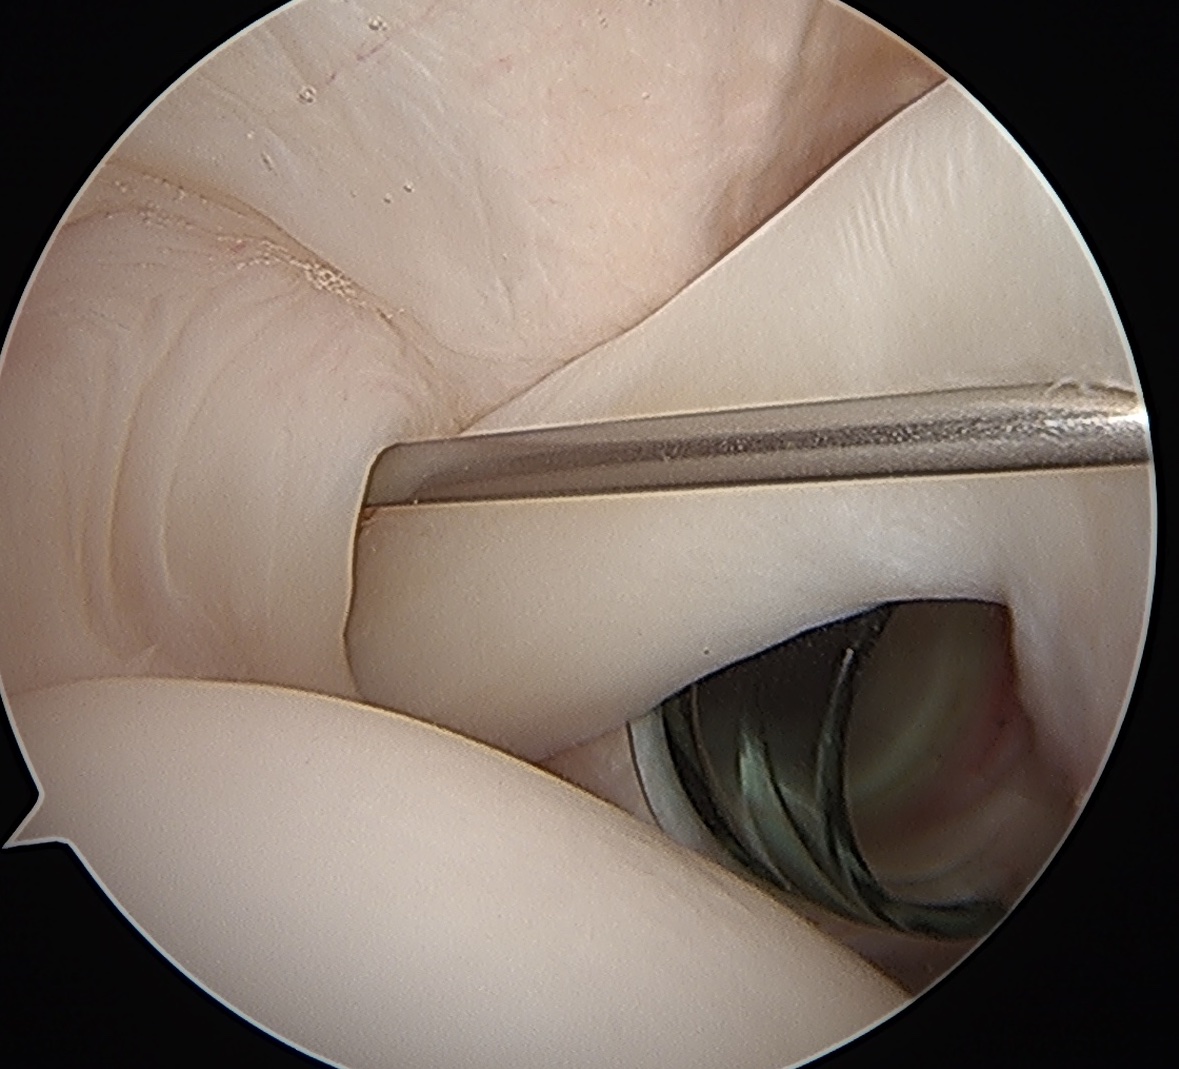

Portal just anterior to supraspinatus tendon

Tag biceps and release

Anchor biceps tendon into bicipital groove